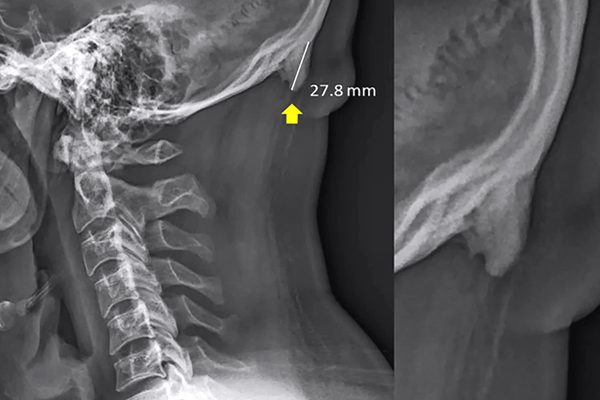

A recent report from BBC shows possible future impacts of technology on the human skeleton says that humans are growing a horn-like structure on their skulls because of excessive usage of mobile phones. The Spurs are a result of pressure exerted on the neck and spine when looking down at a smartphone, as per researchers. "The bump is a sign of sustained terrible posture, which can be corrected quite simply,” Dr. Mark Sayers said in a statement to 9 News.

(Image Source: Washington Post)

The Spurs are actually a subject of worry because it will be a big evolutional change in human skeletal structure.